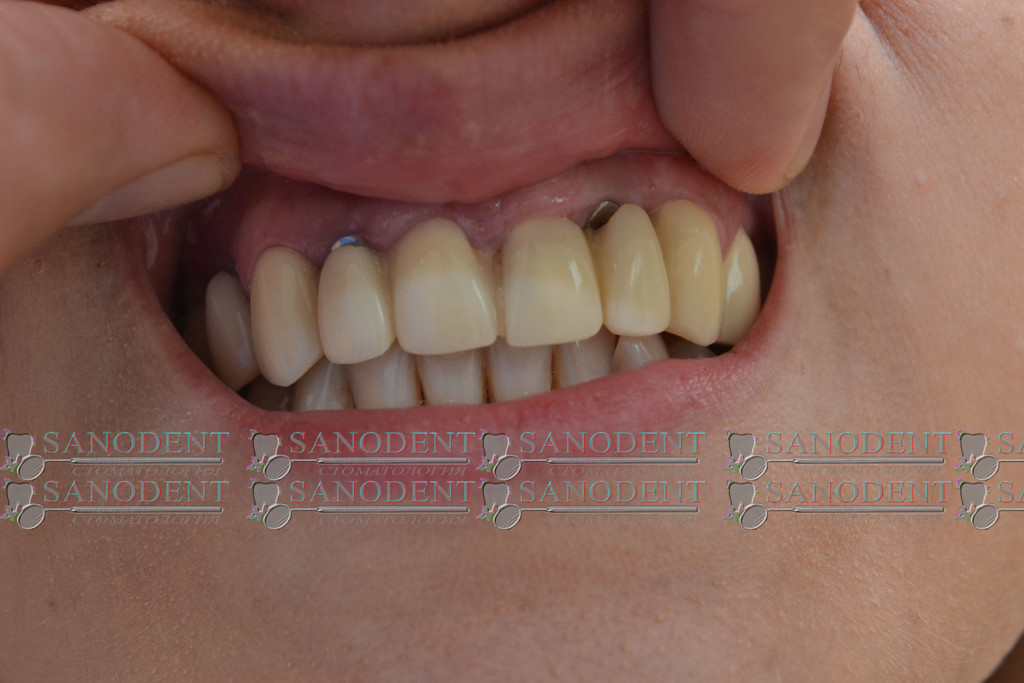

Тотальное протезирование двух челюстей, безметалловые коронки E-max, установленные на вживленные имплантаты Ankylos Dentsply Friadent.

- вживленные имплантаты

- результаты протезирования